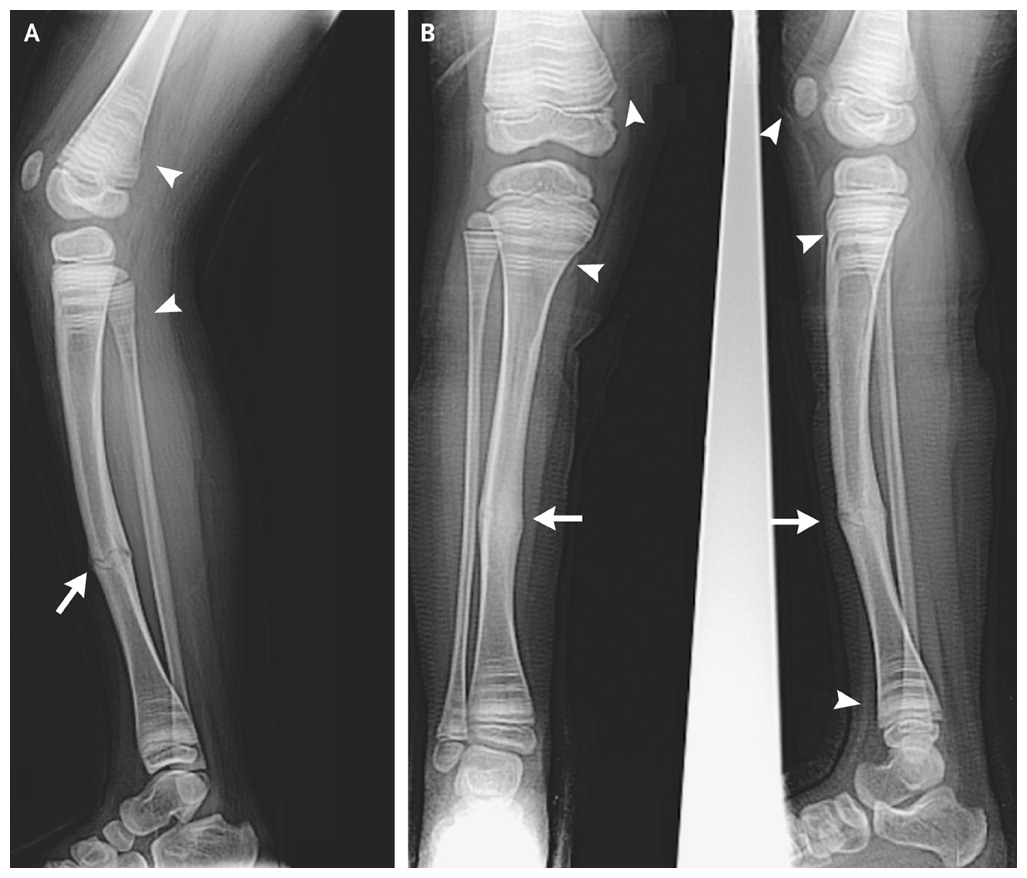

Несовершенный остеогенез типы

Несовершенный остеогенез типы 112 фотографий